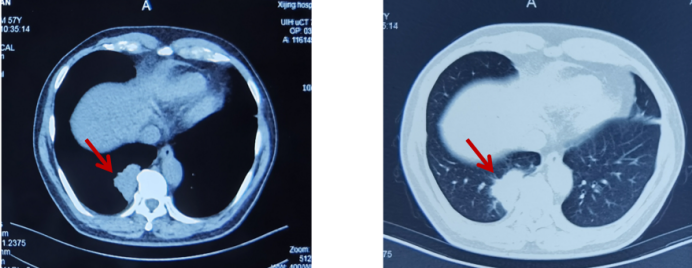

骨骼是肺癌常见的转移部位之一,骨转移癌会导致骨痛、病理性骨折、脊髓压迫、高钙血症等骨相关事件(SRE),其中,骨痛是骨转移癌最常见的临床症状,严重影响患者生活质量。地舒单抗,首个落户中国的核因子κB受体活化因子配体(RANKL)抑制剂,为防治SRE提供新的选择。本次分享地舒单抗治疗以骨痛为主要症状的EGFR突变晚期肺癌骨转移患者案例,希望为SRE的防治带来启迪与思考。 白引苗 空军军医大学第一附属医院肿瘤科 主治医师 中国抗癌协会肿瘤标志物专业委员会 委员 陕西省抗癌协会肿瘤化疗专业委员会 委员 陕西省抗癌协会肿瘤热疗专业委员会 委员 陕西省抗癌协会多原发和不明原发肿瘤专业委员会委员 擅长食管癌、胃癌、结直肠癌、胰腺癌等消化系统、肺癌及妇科常见恶性肿瘤的化疗、靶向治疗及免疫治疗等内科治疗。参译著作1部,参编著作1部,发表核心期刊论文多篇。 一般资料:患者男性,60岁 主诉:右侧肩部疼痛 现病史:2019年8月因右侧肩部疼痛于外院就诊,疼痛NRS评分3-4分,口服依托考昔症状可缓解 个人史:否认吸烟、饮酒嗜好 家族史:1兄因“胃癌”病故 辅助检查: 外院右肱骨MRI:右侧肱骨骨转移可能,合并肱骨中段骨质破坏。 外院胸部CT(图1):右肺下叶周围型肺癌,可疑肺门、纵隔淋巴结转移,T3/4/8椎体骨转移。 图1 胸部CT(箭头指示右肺下叶病变) PET/CT(18F-FDG)(图2-3):右肺下叶基底段软组织病变(3.7 cm×4.6 cm×4.7 cm,SUV max 6.9,平均值6),浅分叶、边缘见毛刺;右侧锁骨上下区、隆突区稍大淋巴结(长径0.6 cm-1.4 cm,SUV max 2.5-4.6,平均值2.2-3.2),考虑转移;脊柱多个椎体及附件、双侧多个肋骨、骨盆多处、双侧股骨上段多发骨质破坏(SUV max 2.0-5.7,平均值1.7-3.9),考虑转移。 图2 PET/CT提示右肺下叶基底段病变及右锁骨上下区、隆突区稍大淋巴结 图3 PET/CT提示多发骨质破坏 患者接受CT引导下经皮右肺病变穿刺活检,病理(图4):光镜见异型细胞呈条索状、腺管样排列,细胞核大、深染,异型性明显;免疫组化:AE1/AE3(+),CK5/6(-),CK7(+),CK8/18(+),P40(-),P63(-), Napsin A(+),ALK(D5F3 Ventana IHC)(-),TTF-1(+),Ki67 30%,支持腺癌。 肿瘤标志物:CYFRA21-1 5.8 ng/ml(参考值:0-3.3 ng/ml),CEA、SCC、NSE正常。 基因检测:EGFR基因19del突变。KRAS、NRAS、PIK3CA、BRAF、HER-2基因未检测到突变;ALK、ROS1、RET基因未检测到融合。 诊断:肺恶性肿瘤(右侧,腺癌,cT2N3M1,IV期,EGFR 19del);骨继发恶性肿瘤(多发);淋巴结继发恶性肿瘤(多发)。 双管齐下、并驾齐驱——抗癌治疗与唑来膦酸齐头并进 2019年9月患者接受奥希替尼80 mg/日一线治疗,同时接受唑来膦酸4 mg/月改善SRE。1个月后复查CT示右肺病变缩小40%(4.7 cm至2.8 cm);肿瘤标志物CYFRA21-1由5.8 ng/ml降至3.67 ng/ml;右肩部疼痛消失(停用止痛药)。 2020年3月复查胸部CT(图5)提示:肺部病变进展(增大39.3%,2.8 cm至3.9 cm);肿瘤标志物CYFRA21-1缓慢升高至7.05 ng/ml。考虑局部进展,在奥希替尼基础上联合培美曲塞+卡铂治疗4个周期,后给予奥希替尼联合培美曲塞维持治疗14个周期。 图5 胸部CT(2020年3月,箭头指示右肺病变) 最佳疗效:右肺病变缩小51.3%(至1.9 cm)(图6);肿瘤标志物CYFRA21-1由7.05 ng/ml降至1.4 ng/ml。 图6 二线治疗前(左图)后(右图)胸部CT比较(箭头指示右肺病变) 2021年4月患者感背部钝痛,NRS评分5-6分,口服氨酚羟考酮330 mg/8 h,症状可缓解。骨扫描(ECT)与单光子发射计算机断层扫描(SPECT)/CT提示骨转移加重。停用唑来膦酸,使用地舒单抗120 mg/月,疼痛有缓解。 2021年9月复查胸部CT示右肺下叶病变进展(1.9 cm至3.4 cm)。肿瘤标志物CYFRA21-1由10.73 ng/ml升至13 ng/ml。患者感背部疼痛加重,NRS 评分5-6分。行CT引导下右肺病变再次穿刺活检,病理提示肺腺癌,PD-L1(SP263)(TPS=80%),Ki67 85%。基因检测:EGFR 19del,KRAS、NRAS、PIK3CA、BRAF、HER-2基因及MET exon14无突变;ALK、ROS1、RET基因无融合。 遂调整为白蛋白结合型紫杉醇化疗2周期,奥希替尼和地舒单抗方案同前,患者背部疼痛消失。 2021年11月复查PET/CT:原右肺下叶基底段团块状软组织病变较初诊缩小(1.8 cm×1.6 cm×3.8 cm);原右侧锁骨区多发淋巴结消失;原隆突区稍大淋巴结缩小(0.5 cm);原脊柱多个椎体及附件、双侧多个肋骨、骨盆多处、双侧股骨上段多发骨质破坏,病变密度增高,考虑治疗有效,部分仍有代谢活跃;右侧颞叶片状低密度影。查头颅MRI(图7):左侧额叶大脑镰旁(0.7 cm×0.7 cm×1 cm)、右侧颞叶脑皮质表面(1.2 cm×1.3 cm×0.8 cm)异常强化灶,考虑转移。 图7 头颅MRI(箭头指示颅内病变) 经MDT讨论,建议脑部病变随诊观察。鉴于出现脑转移癌,调整为伏美替尼80 mg/日口服、白蛋白结合型紫杉醇静脉化疗;继续予地舒单抗。 患者治疗期间碱性磷酸酶(ALP)水平变化如图8所示。 图8 血清碱性磷酸酶变化情况 患者于2019年8月因右侧肩部疼痛就诊,确诊右肺腺癌Ⅳ期伴多发骨转移及淋巴结转移,EGFR 19del突变。一线治疗:奥希替尼(80 mg/日)+骨改良药物唑来膦酸(4 mg/月),最佳疗效:右肺肿瘤PR(缩小40%)、疼痛症状缓解,一线治疗PFS时间7个月。2020年3月,肺部病灶进展,予奥希替尼+培美曲塞联合卡铂4周期,后培美曲塞维持治疗14周期,继续予唑来膦酸治疗;2021年4月背部钝痛加重,骨扫描提示骨病变进展,遂停用唑来膦酸,予地舒单抗120 mg/月治疗至2021年9月,二线PFS 18个月。后因肺部病灶进展,三线治疗给予奥希替尼+白蛋白结合型紫杉醇及地舒单抗,患者背部疼痛症状消失。2021年11月头颅MRI示颅内转移,调整为予伏美替尼(80 mg/日)联合白蛋白结合型紫杉醇及地舒单抗治疗。 张红梅 西京医院肿瘤科主任 肿瘤学博士,硕士研究生导师 中国抗癌协会CMUP 副主委 中国临床肿瘤学会免疫专家委员会 常委 陕西省医学会肿瘤内科分会 副主委 主要从事肺癌等恶性肿瘤的内科治疗 我国肺癌发病率和死亡率均位于恶性肿瘤首位,20%-30%的晚期肺癌会发生骨转移[1],45%的肺癌骨转移患者会出现相关临床症状[2]。肺癌骨转移是患者生活质量降低、生存期缩短的独立危险因素,SRE如骨痛、病理性骨折、脊髓压迫等,不仅给患者带来生理上的痛苦与不便,也引发患者心理打击。因此,对于晚期肺癌骨转移患者,在控制原发疾病同时,亟需积极防治SRE,以达到提高患者生活质量、缓解生理心理痛苦、延长生存期的目的[3]。 本例肺癌同时性骨转移案例,以骨痛为首发症状,在奥希替尼治疗肺癌同时,首先予以唑来膦酸防治SRE,治疗初期患者症状一度改善。但随着疾病进展,唑来膦酸应用近20月后患者再次骨痛加重,影像学提示骨损害加重,对于这种骨病变进展、骨痛加重的临床问题,如何制定进一步治疗方案? 地舒单抗是IgG2型单克隆抗体,通过与RANKL结合,阻止其激活破骨细胞、破骨细胞前体和破骨细胞样巨细胞表面的核因子-κB受体活化因子(RANK),从而达到抑制肿瘤生长、减少骨破坏的目的。早在2010年,地舒单抗获得美国食品药品监督管理局(FDA)批准用于治疗实体瘤骨转移,目前已积累了丰富的证据临床研究和真实世界数据,显示其有效性和安全性。 地舒单抗与唑来膦酸治疗实体瘤骨转移和多发性骨髓瘤的Ⅲ期临床研究显示,地舒单抗可延缓首次出现SRE的时间(21.4个月 VS. 15.4个月)[4]。其中非小细胞肺癌患者,地舒单抗组较唑来膦酸组中位生存期(OS)延长1.5个月(9.5个月 VS. 8.0个月)[5]。安全性方面,地舒单抗也具有一定的优越性:与唑来膦酸组比较,地舒单抗组贫血、厌食症、肾脏不良事件、新发原发性恶性肿瘤的发生率较低[6]。地舒单抗通过网状内皮系统清除,不增加肾脏负担,对于肾功能不全的患者可作为首选。此外,作为皮下注射制剂,28天用药一次,无需住院完成,无疑为口服靶向药的肺癌骨转移患者带来极大的便利。 本例患者经唑来膦酸治疗后再次出现SRE,改用地舒单抗治疗至今,患者骨痛症状缓解,随访血清ALP水平逐渐下降,且耐受性良好。对这位长期与肺癌抗争的晚期患者,地舒单抗减轻了身体的疼痛,带来心灵的慰藉,实现临床获益。 2020年11月20日,地舒单抗在中国获得国家药品监督管理局(NMPA)批准,用于预防实体瘤骨转移及多发性骨髓瘤引起的SRE,随着药物可及性的进一步提高,期待地舒单抗可造福更多饱受骨转移折磨的中国肿瘤患者。 参考文献 1、Her nandez R K , Wade S W, Ly man GH, et al. I ncidence of bone metastases in patients with solid tumors: analysis of oncology electronic medical records in the United States. BMC Cancer, 2018, 18(1): 44. 2、Tsuya A, Kurata T, Tamura K, et al. Skeletal metastases in non-small cell lung cancer: a retrospective study. Lung Cancer, 2007, 57(2): 229-232. 3、北京医学奖励基金会肺癌青年专家委员会,中国胸外科肺癌联盟. 肺癌骨转移诊疗专家共识(2019版)[J]. 中国肺癌杂志, 2019, 22(4): 187-207. 4、Henry D, Vadhan-Raj S, Hirsh V, et al. Delaying skeletal-related events in a randomized phase 3 study of Denosumab versus zoledronic acid in patients with advanced cancer: an analysis of data from patients with solid tumors. Support Care Cancer. 2014 Mar; 22(3): 679-687. 5、Scagliotti GV, Hirsh V, Siena S, et al. Overall survival improvement in patients with lung cancer and bone metastases treated with Denosumab versus zoledronic acid: subgroup analysis from a randomized phase 3 study. J Thorac Oncol. 2012 Dec; 7(12): 1823-1829. 6、Fengxia Chen, Feifei Pu. Safety of Denosumab Versus Zoledronic Acid in Patients with Bone Metastases: A Meta-Analysis of Randomized Controlled Trials. Oncol Res Treat. 2016;39(7-8):453-459.基本情况